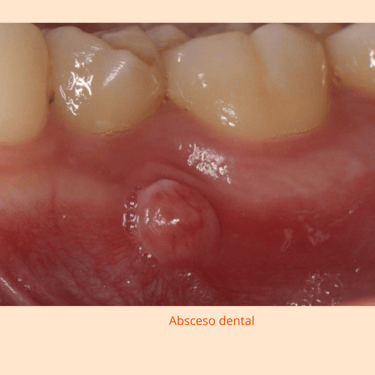

Las lesiones periapicales son infecciones crónicas que se desarrollan alrededor de la raíz del diente, generalmente debido a una infección no tratada en la pulpa dental. Se manifiestan como dolor, hinchazón o un absceso.

Importancia: Las lesiones periapicales, como abscesos y granulomas, se forman en el extremo de la raíz del diente. Tratarlas a tiempo es crucial para prevenir la propagación de la infección y la pérdida del diente.